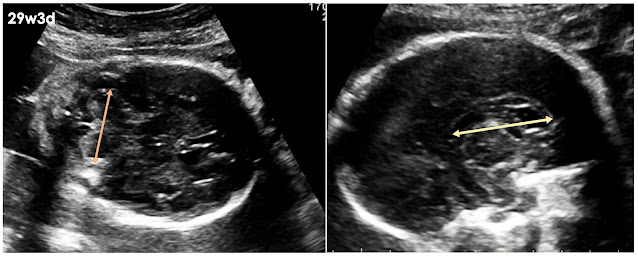

| (圖一)個案顱窩看到高回音的血栓(橘色箭頭)被包覆在擴大的靜脈竇(黃色箭頭)裡面,懷疑是硬腦膜靜脈竇血栓(dural sinus thrombosis) |

此次MRI季會中,討論到一個產前比較少見的疾病,硬腦膜靜脈竇血栓(Dural sinus thrombosis)。個案29週於外院產檢被懷疑胎兒合併腦部腫瘤,29週3天轉診到台兒診所尋求第二意見。超音波影像上,後顱窩的部位可見一高回音的腫塊被包覆在無回音的三角形空腔內(圖一),根據病灶的型態及位置,懷疑是硬腦膜靜脈竇血栓(dural sinus thrombosis),高回音的腫塊為血栓,三角形空腔則為擴大的靜脈竇。另外,可見雙側側腦室擴大,左側為中度,右側為輕度(左:13.3mm, 右:10.6mm)(圖二),懷疑是因擴大的靜脈竇壓迫而導致,腦部其餘部份結構正常(圖三)。